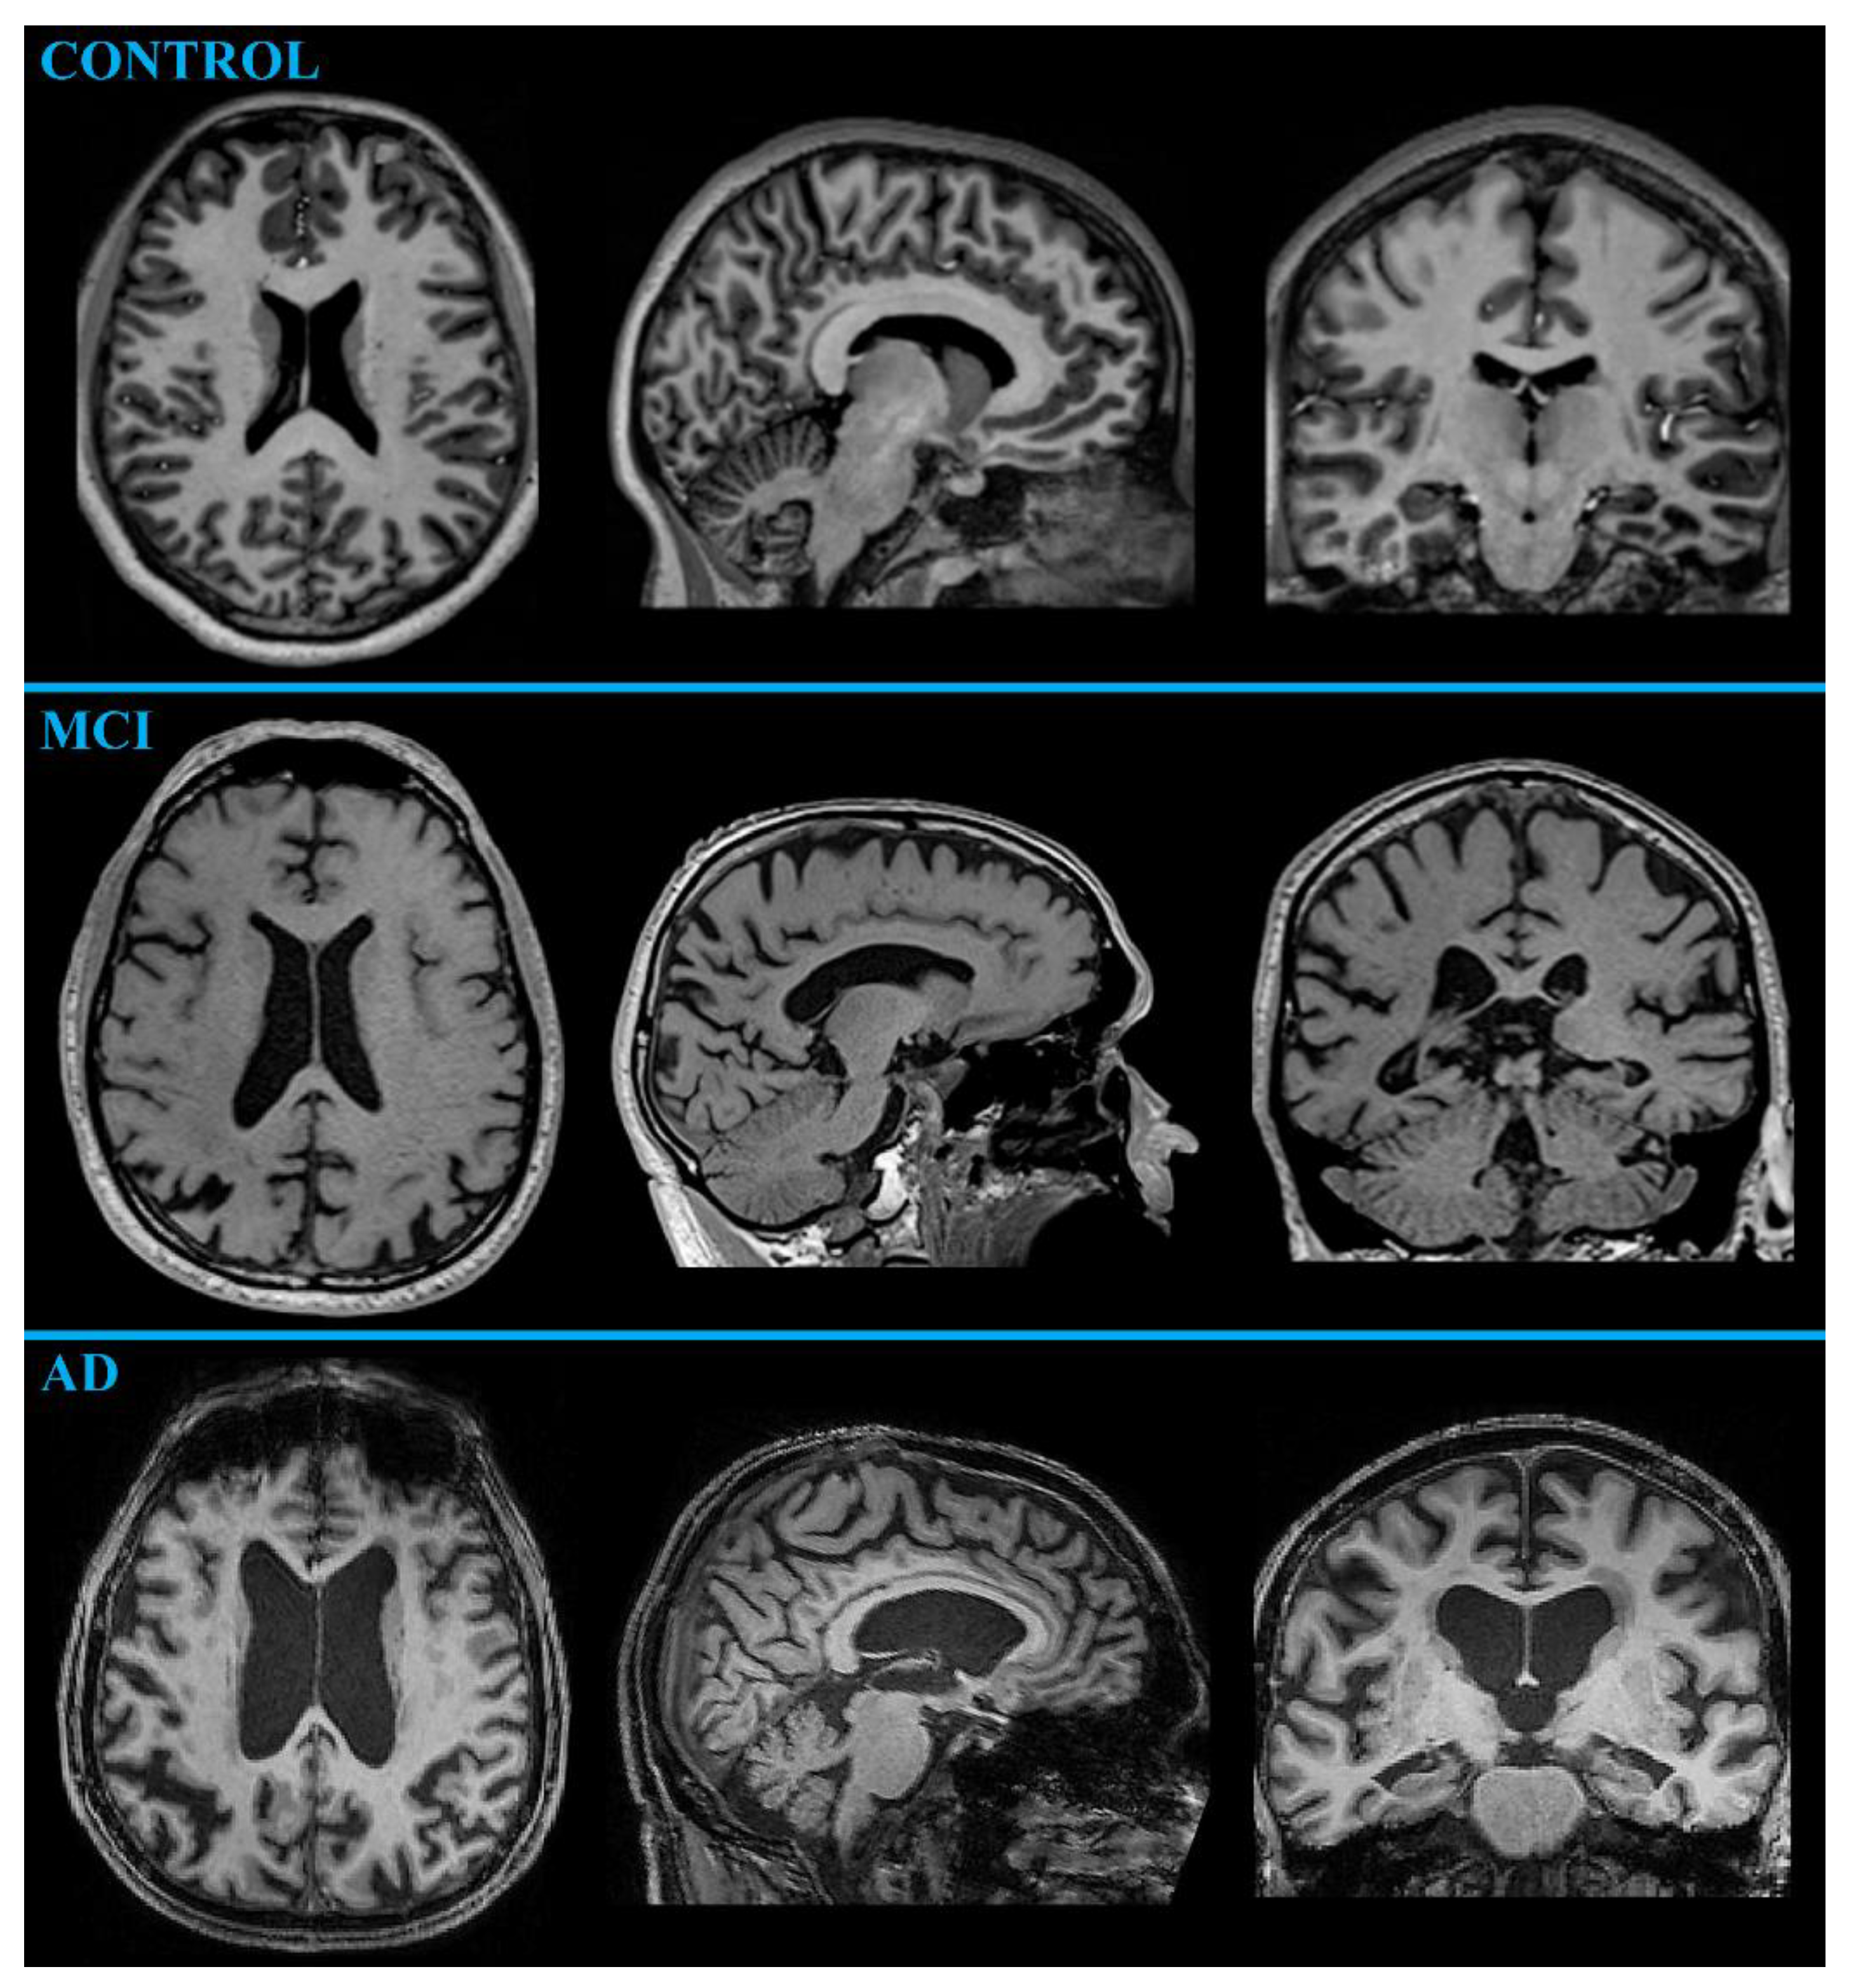

MR-Volumetry

- Chandra, A.; Dervenoulas, G.; Politis, M.; Alzheimer’s Disease Neuroimaging, I. Magnetic resonance imaging in Alzheimer’s disease and mild cognitive impairment. J. Neurol. 2019, 266, 1293–1302. [Google Scholar] [CrossRef] [PubMed]